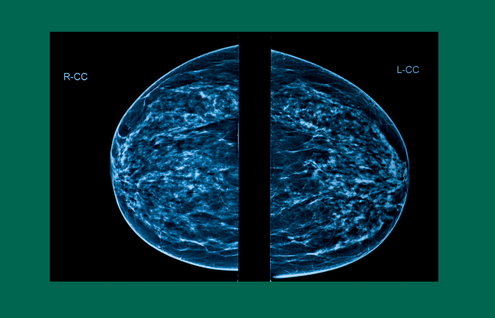

“When a breast has more breast and connective tissue than it does fat, it’s considered a dense breast. While they don’t feel different or look different to the naked eye than a non-dense breast, dense breasts do look different on mammogram imaging.”

“Both cancer and fibrous tissues appear lighter gray on a mammogram,” says DiSano, “which can make it very hard to read the imaging. But fortunately, there are alternative imaging options available.”